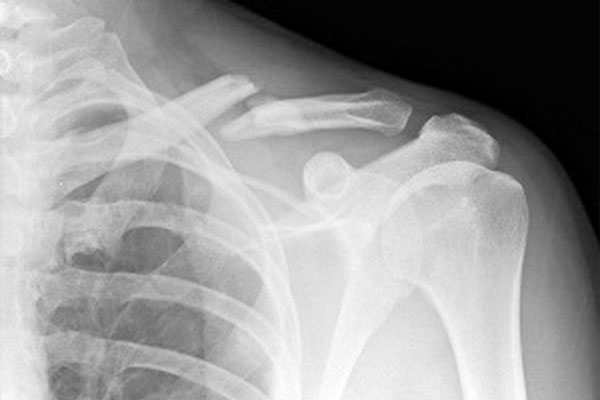

كسر القدم هو كسر أو كسر في أحد عظام القدم. الأسباب الأكثر شيوعًا هي السقوط وحوادث السيارات والإصابات الرياضية.